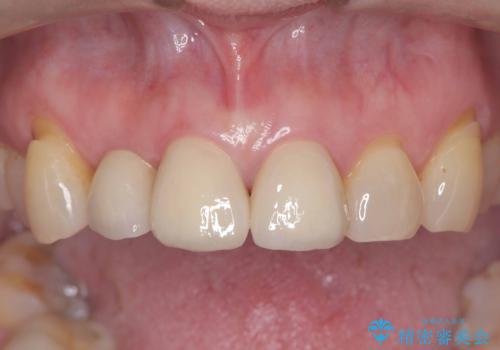

[ セラミック治療 ] 前歯の見た目を改善したい

![[ セラミック治療 ] 前歯の見た目を改善したいの症例 治療後](https://seimitsushinbi.jp/wp/wp-content/uploads/2025/10/IMG_9934-500x350.jpg?v=1761816431)